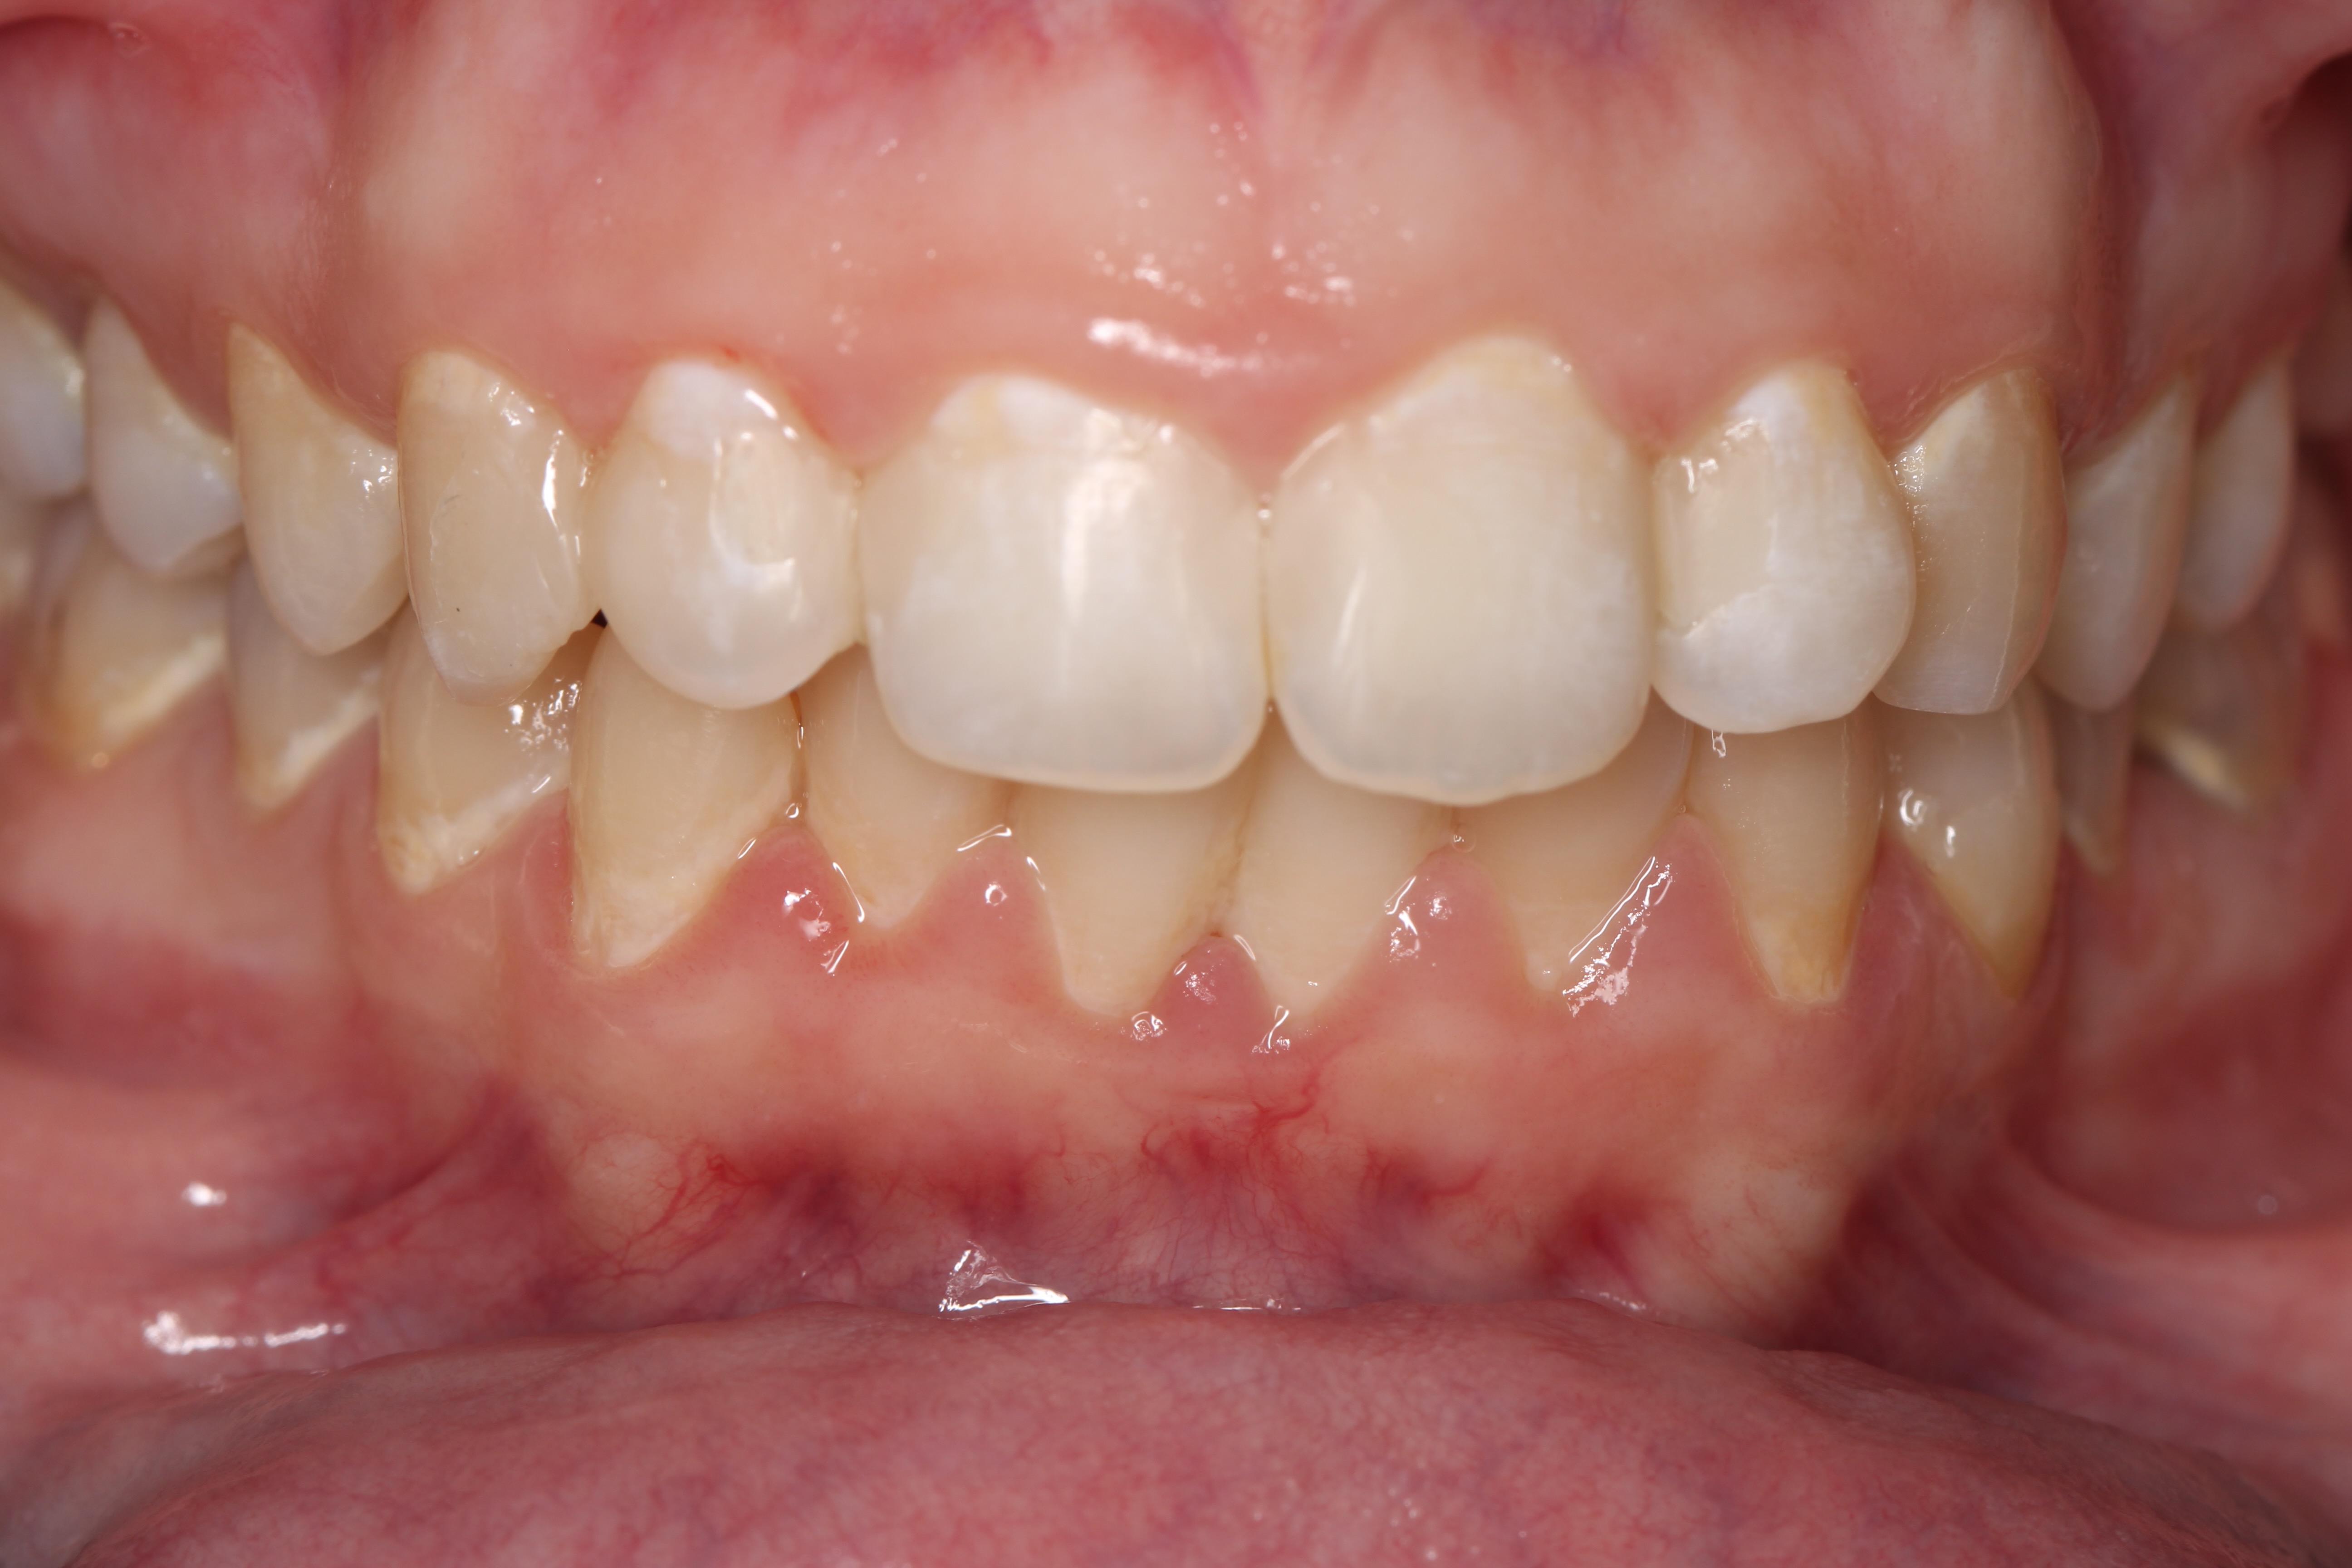

Anterior ceramic crowns and smile design by Mr Stefano Del Monte

From this course, I learned the whole workflow involving designing crowns for an aesthetic case. I learned how to work alongside the lab to create digital smile wax-ups, how to manage patient expectations and prepare teeth quickly and effectively for anterior crowns and veneers.play your timeline of professional development